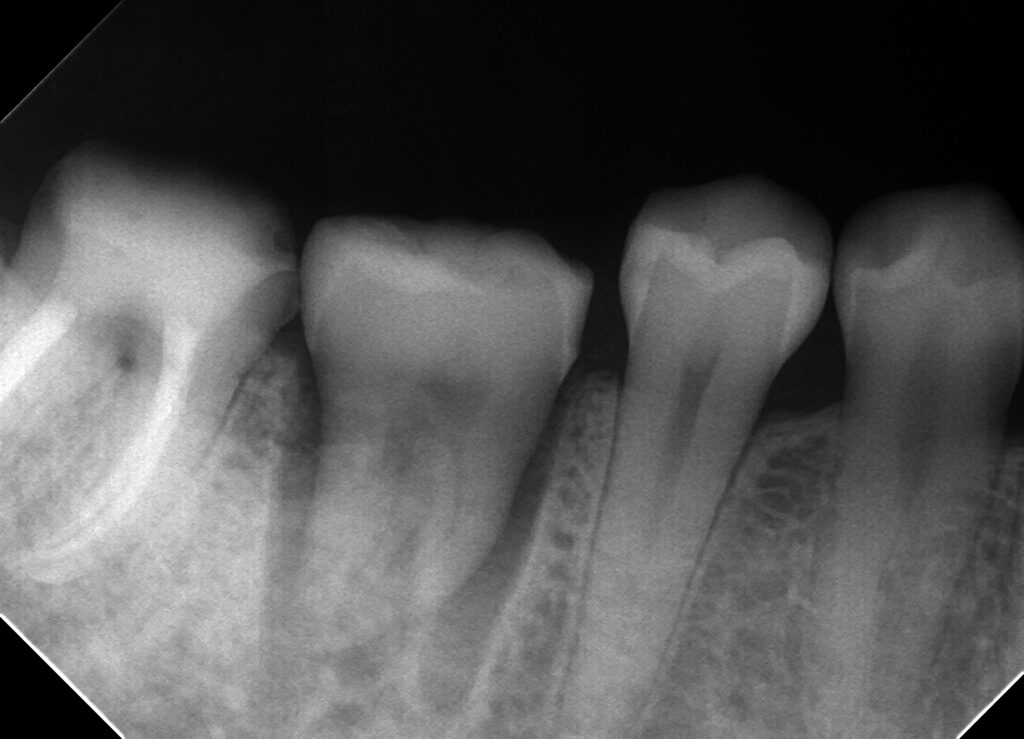

これは右下6が歯根破折して他院で抜歯といわれインプラントを勧められた症例です。

当院の診断でも抜歯後インプラントが一番ベターな方法だと思い、説明させていただきましたが

やはり費用、自分の歯で噛みたいという希望が強かったので歯牙移植術をしてみました。

今後は根っこの治療を行い、もし生着するようであればまた報告したいと思います!